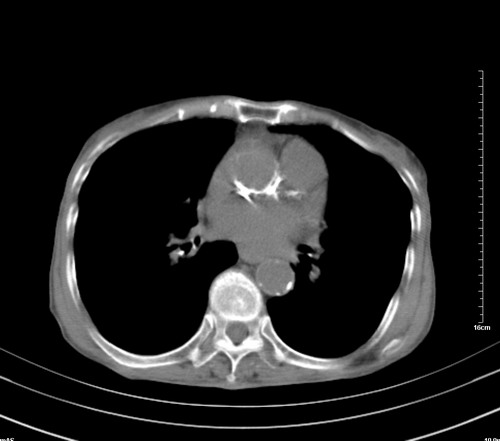

病人,女,79岁,主要因腹疼二月入院,彩超,肝,胆,脾,未见异常,胸透上消化道造影未见异常,化验白细胞增高,内科医生让做胸部ct检查,因为熟人多做了腹部(外科会诊考虑胆囊炎).现ct片如下请假各位战友.

中后纵隔占位,气管、食道受压、变形、移位。恶性可能性大。

考虑:中后纵隔转移瘤可能性大,主动脉硬化。

1 气管旁、隆突下淋巴结明显肿大,肝左叶外侧段低密影,都考虑转移。

肺癌,纵隔淋巴结转移,肝左叶病变考虑为转移病灶。

后中纵隔团块影,伴气管、食道受压移位,首先考虑转移瘤,肝s5段低密度灶。建议增强检查,另外其结肠是否有问题请提供,右肺部分肺叶局限含气增多,考虑局限肺气肿。

后中纵隔团块影,伴气管、食道受压移位,首先考虑转移瘤,肝表现同11773。